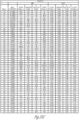

- FIG. 32A-32D illustrate a series of tables of the summary of the results of the MID immunoassay of FIGS. 25A-25H and 26A-26R.

- FIG. 32A is a summary table of the results of synovial fluid reactivity in the Staphylococcus aureus (Panel A) assay and Staphylococcus epidermidis (Panel B) assay.

- FIG. 32B is a summary table of the results of synovial fluid sample reactivity in the Enterococcus faecalis assay

- FIG. 32C is a summary table of the results of synovial fluid reactivity in the Candia Panel assay.

- FIG. 32A is a summary table of the results of synovial fluid reactivity in the Staphylococcus aureus (Panel A) assay and Staphylococcus epidermidis (Panel B) assay.

- FIG. 32B is a summary table of the results of synovi

- 32D is a summary table of the results of synovial fluid sample reactivity of the Candida Panel across several species of Candida.

- Staphylococcus represent 65% of all culture positive (S. aureus, S. epidermidis and S. lugdenensis account for 90% of all Staphylococcus PJI.

- Staph Panel B Specificity 100% (103/103 AD-/Cul-/CRP-); 100% (139/139 AD-/Cul-/CRP-, + non-Staph species).

- Enterococcus faecalis Specificity 99.0% (102/103 AD-/Cul-/CRP-); 96.4% (134/139 AD-/Cul-/CRP-, + non-E. faecalis species).

- Candida Panel Specificity 100% (103/103 AD-/Cul-/CRP-); 100% (139/139 AD-/Cul-/CRP-, + non-Candida species).